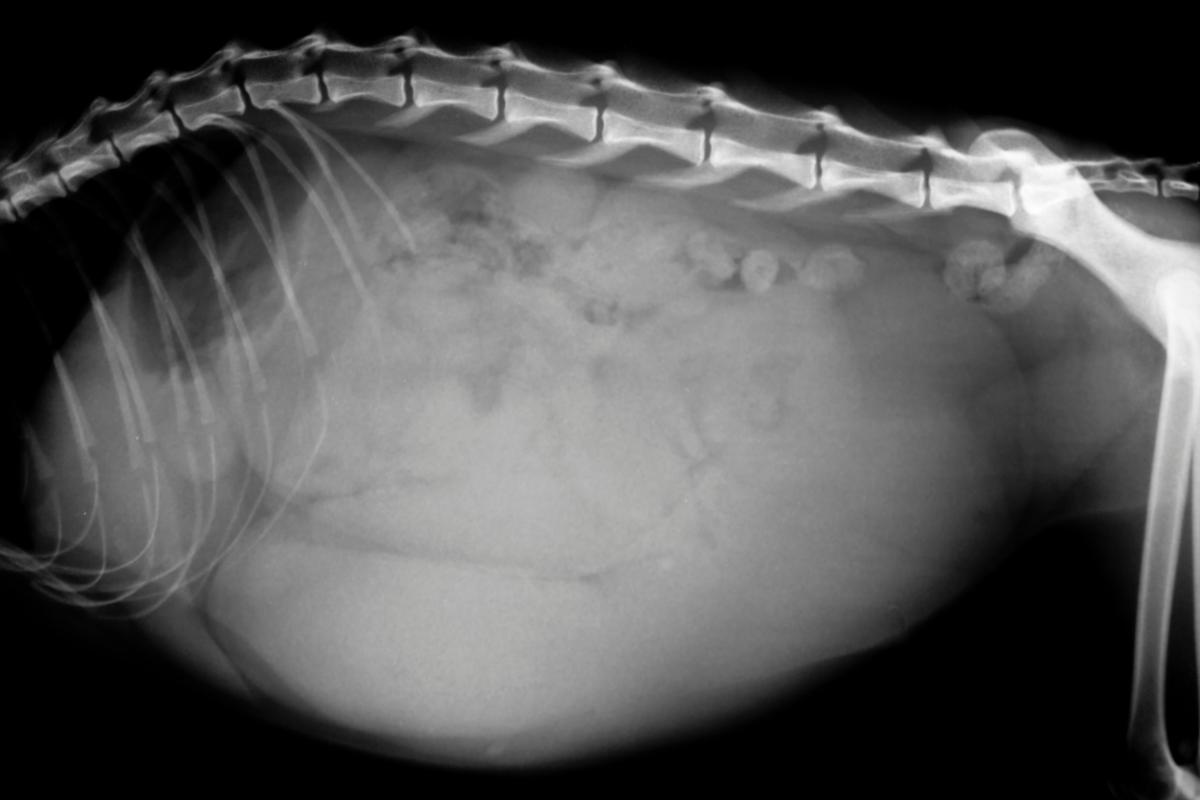

Piometra

Por último, vamos a incluir la piometra en este listado de enfermedades con alto riesgo de resultar fatales. No parece que la piometra o infección uterina sea una enfermedad que mata a los perros, en este caso, a las perras, pero lo cierto es que sí puede resultar mortal, especialmente en su presentación cerrada, pues podemos no detectarla hasta que ya sea demasiado tarde.

Así, la piometra es la infección del útero que pueden sufrir las hembras enteras, sobre todo a partir de los 6 años. El útero aumenta de grosor y se llena de líquido por acción de la progesterona, que está elevada en las 8-10 semanas posteriores al celo. Esta situación se conoce como hiperplasia endometrial quística y crea un ambiente ideal para el crecimiento de las bacterias. Por este motivo, si consiguen entrar en el útero, se producirá la infección que llamamos piometra, en los 30-60 días después del celo. Las perras con esta enfermedad pueden mostrar estos signos clínicos:

Como hemos dicho, hay una piometra cerrada y otra abierta. En la abierta, como su nombre indica, el útero se abre y veremos un manchado vaginal, como una sopa de tomate, que debe llevarnos a buscar asistencia veterinaria. Esta apertura favorece que la piometra sea menos grave. Al contrario, en la piometra cerrada, como no hay salida para el contenido del útero, este aumenta de tamaño, provocando inflamación y dolor en el abdomen. Estas perras corren mucho riesgo, tanto porque tardemos en prestarles asistencia veterinaria como porque ya sea tarde debido a la gravedad de la infección o a la potencial rotura uterina.